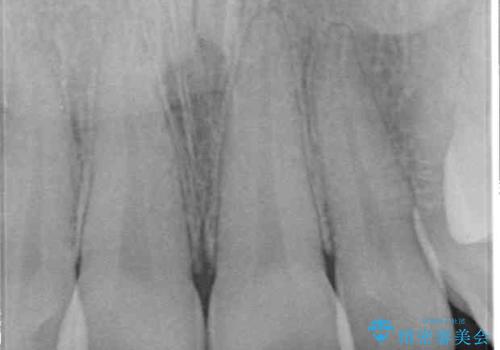

捻れた出っ歯の前歯 オールセラミッククラウンによる審美治療

- 前歯が捻れており出っ歯であることを気にして来院された患者様です。

虫歯がほとんどなく、前歯以外にも歯列に問題があったため、歯列矯正を第一選択として強く勧めました。

補綴治療に先立ち、歯の形態を修正する必要があったため、残念ではありますが根管治療を行うこととしました。